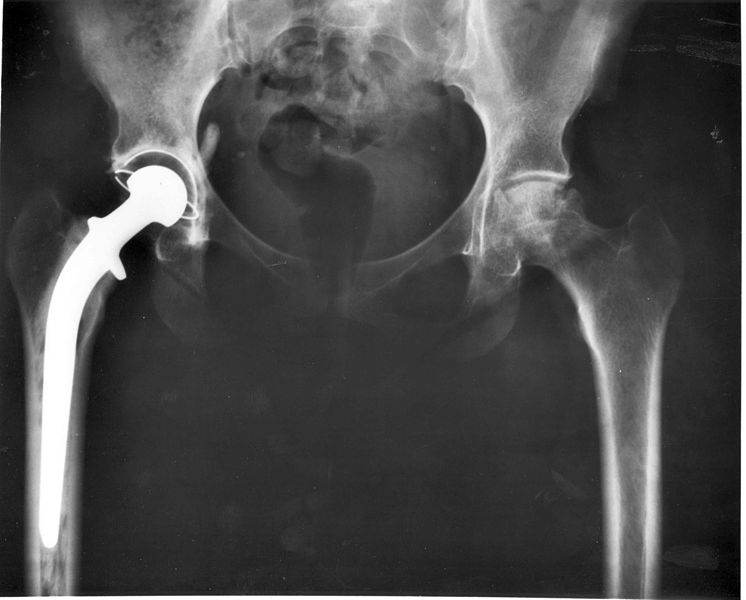

A hip replacement is a common type of surgery where a damaged hip joint is replaced with an artificial one (known as a prosthesis).

The surgeon makes an incision into the hip, removes the damaged hip joint and then replaces it with an artificial joint that is a metal alloy or, in some cases, ceramic.